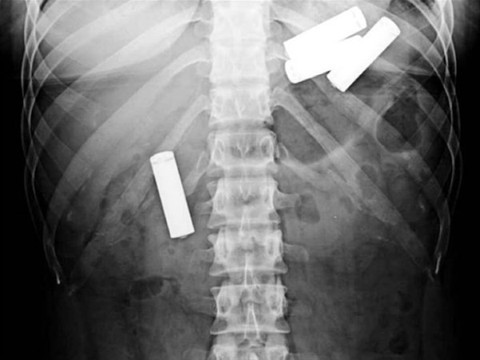

Cinsel İlişki oyuncağı bağırsaklarına kaçtı çıkarmayı denedi ama... Galerinin tamamı için tıklayınız 13 aylık bir bebeğin yuttuğu piller.